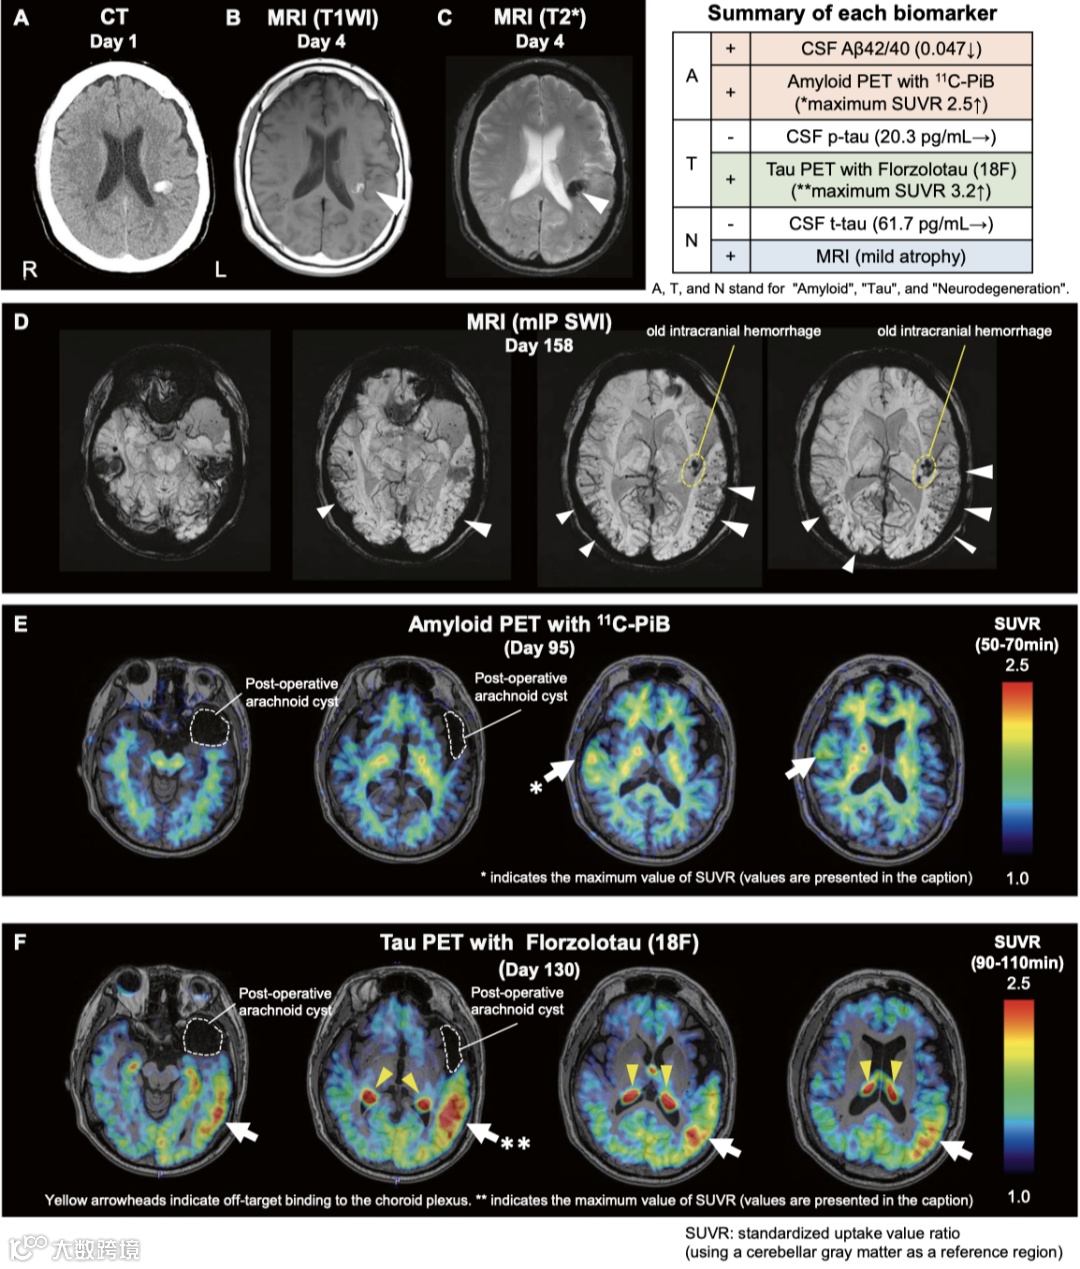

一名39岁男性以构音障碍和右腿麻木为主诉就诊,这些症状反复出现并迅速缓解。CT显示左顶叶血肿(图1A)。脑电图显示局灶性尖波,症状在抗癫痫药物治疗后消失,提示癫痫。既往病史包括1岁时左颞叶蛛网膜囊肿手术治疗和尸体硬脑膜(材料由Lyodura提供)移植。MRI显示脑叶出血及皮层下区域的多发微出血,呈现出不典型的脑淀粉样血管病(CAA)表现,并伴有显著的非对称性(图1A-D)。

脑脊液分析显示细胞计数、蛋白质水平、总和磷酸化tau 蛋白正常,并且淀粉样β42/40比值降低。脑脊液14–3-3 蛋白水平和朊病毒的实时震动诱导转化实验均正常。基因分析显示APOE ε3/ε3 野生型基因型,未发现APP/PSEN1/PSEN2/APOE突变。以上结果提示患者CAA非朊病毒病或家族性阿尔茨海默病引发的可能性极低,而因硬脑膜移植物引发的医源性CAA可能性更大。淀粉样蛋白PET 显示在硬脑膜移植对侧的某些灰质区域有局部摄取(图1E),而tau PET 则在同侧皮层显示出显著的摄取(图1F)。

图1.医源性CAA患者的多模态影像

在医源性CAA 中,曾报告过淀粉样蛋白PET 的双侧积累;然而,尚未报告过对侧的局部积累。虽然在医源性CAA 的尸体脑评估中已报告过tau 蛋白存在,但这是首次通过体内PET 提示 tau蛋白沉积。对侧淀粉样蛋白积累提示病理蛋白通过血流或脑脊液流动传播,而非直接传播。相反,同侧tau 蛋白成像则提示从尸体硬脑膜移植侧直接发生tau蛋白沉积。